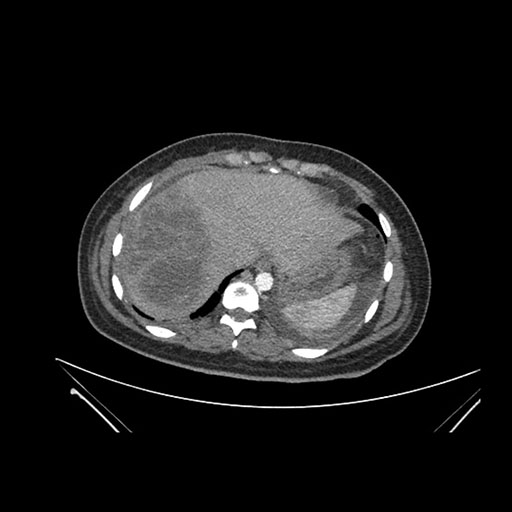

Axial Arterial

Axial Venous